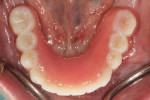

A patient presented to the author's clinical practice with an existing maxillary complete denture and mandibular implant overdenture (Figure 1). The patient indicated she was happy with her existing dental treatment but was looking for an option of mandibular teeth that are not removable. Intraoral examination reveals that she has been treated with four dental implants (Legacy 3, Implant Direct) with overdenture abutments (LOCATOR R-Tx, Zest Dental Solutions) in approximately the first molar and lateral incisor region (Figure 2). She was presented with several options, including a screw-retained restoration with denture teeth and a titanium framework; a monolithic zirconia screw-retained full-arch; and a screw-less fixed full-arch hybrid solution. The patient indicated that, because she travels more than 5 hours to the author's practice, she preferred whatever treatment option would minimize the number of visits to the office. Additionally, she indicated that she had been having mobility issues recently and would prefer a treatment option that could be completed within a 1- or 2-day period to minimize travel back and forth to the office. She and the author discussed the advantages and disadvantages of each of the treatment options and decided on a screw-less treatment option that could be started during that same visit. The author also advised her that she would need to wear a prototype prosthesis for at least a month to confirm that the change from an overdenture to fixed is comfortable prior to fabrication of the final restoration.

Denture attachment housings were removed from the existing implant overdenture, and recesses within the intaglio surface of the prosthesis were enlarged. Light-body PVS (Chairside VPS, Zest Dental Solutions) was injected into the intaglio of the prosthesis and placed onto the edentulous ridge over the abutments. The patient was instructed to close into centric and the prosthesis was border molded to capture the soft tissue borders. After complete polymerization, the prosthesis was removed (Figure 3). The maxillary prosthesis was removed and the existing soft liner removed from the intaglio of the prosthesis. A reline procedure was also completed within the maxillary denture. The patient's mandibular prosthesis was optically scanned 360 degrees around the prosthesis and reline impression using an intraoral scanner (TRIOS, 3Shape). The patient's maxillary dentition was optically scanned, the mandibular prosthesis was replaced onto the edentulous ridge, and an optical scan of the maxillary and mandibular prosthesis in occlusion was captured. Existing overdenture abutments were removed, implants were irrigated with sterile water, and fixed hybrid implant abutments (LOCATOR F-Tx, Zest Dental Solutions) were placed (Figure 4). A panoramic radiograph was made (Green CT, Vatech) to confirm complete adaptation of the abutments to the implants. The abutments were torqued according to the manufacturer's recommendations and housings were placed (F-Tx Denture Attachment Housing, Zest Dental Solutions) (Figure 5). After the housings were manually angled to parallel with the occlusal plane, an optical scan was made of the edentulous arch (Figure 6 and Figure 7). The patient was asked to return later in the afternoon on the same day for definitive procedures.